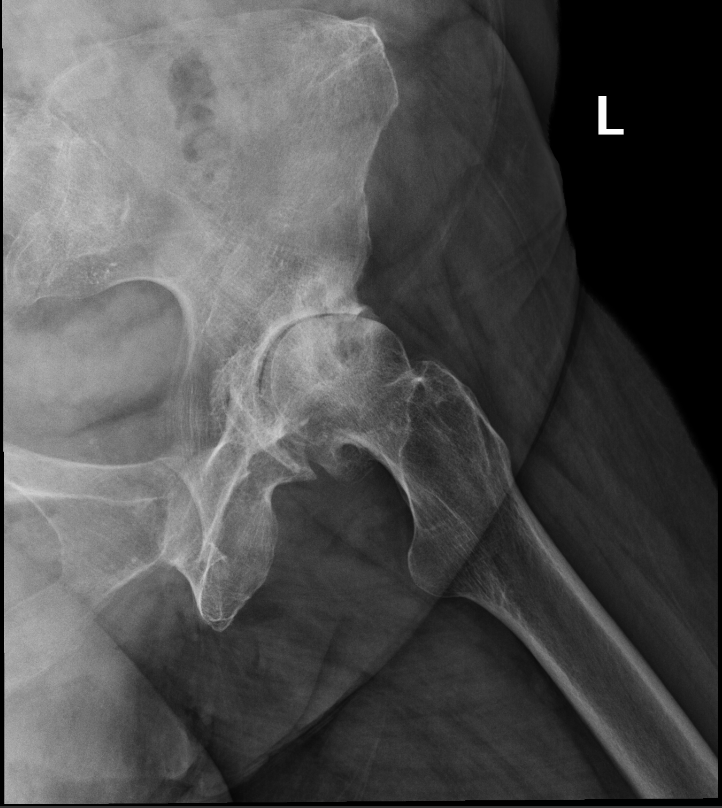

Arthritis is inflammation of the joints resulting in pain, swelling, stiffness and limited movement. Hip arthritis is a common cause of chronic hip pain and disability. The three most common types of arthritis that affect the hip are:

- Osteoarthritis: It is characterized by progressive wearing away of the cartilage of the joint. As the protective cartilage wears down, the bone ends rub against each other and cause pain in the hip. Rheumatoid arthritis: This is an autoimmune disease in which the tissue lining the joint (synovium) becomes inflamed, resulting in the production of excessive joint fluid (synovial fluid). This leads to loss of cartilage causing pain and stiffness.

- Traumatic arthritis: This is a type of arthritis resulting from a hip injury or fracture. Such injuries can damage the cartilage and cause hip pain and stiffness over a period of time.

The most common symptom of hip arthritis is joint pain and stiffness resulting in limited range of motion. Vigorous activity can increase the pain and stiffness which may cause limping while walking.

Diagnosis is made by evaluating medical history, physical examination and X-rays.